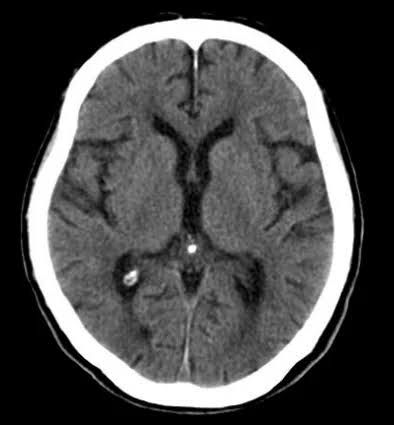

A morte encefálica é a perda completa e irreversível das funções do cérebro e do tronco encefálico. Isso significa que o paciente não tem reflexos neurológicos, não respira por conta própria e não apresenta qualquer atividade cerebral, mesmo que aparelhos mantenham o coração batendo e o corpo aquecido. O coma, por outro lado, é um estado grave, mas potencialmente reversível. Essa diferença é fundamental e precisa ser compreendida por todos.

No Brasil, o diagnóstico de morte encefálica é feito seguindo critérios rígidos estabelecidos pelo Conselho Federal de Medicina e pela legislação federal. São necessárias avaliações clínicas realizadas por dois médicos especialistas independentes, teste de apneia e exame complementar, como eletroencefalograma ou Doppler transcraniano, sempre com protocolos claros que asseguram precisão e transparência.

No entanto, essa sensação é ilusória: o funcionamento cardíaco só persiste graças ao suporte contínuo de aparelhos. Sem eles, o corpo não manteria sozinho nenhuma função vital. A ausência total de atividade cerebral, comprovada por exames e protocolos médicos rigorosos, é o que determina a morte encefálica. Portanto, embora os sinais vitais artificiais transmitam a ideia de vida, a realidade neurológica e legal é de morte completa e irreversível. “Sabemos que esse é um dos momentos mais difíceis para qualquer família. Ver um corpo ainda aquecido, com o coração batendo, traz a sensação de que existe alguma chance. Mas é justamente nesse instante tão doloroso que a medicina precisa entrar com clareza e empatia. A morte encefálica é irreversível, e quando bem compreendida, pode transformar essa dor imensa em um gesto de amor ao próximo. É quando a vida, mesmo na ausência, pode continuar por meio da doação de órgãos”, explica o neurocirurgião Dr. Denildo Veríssimo.